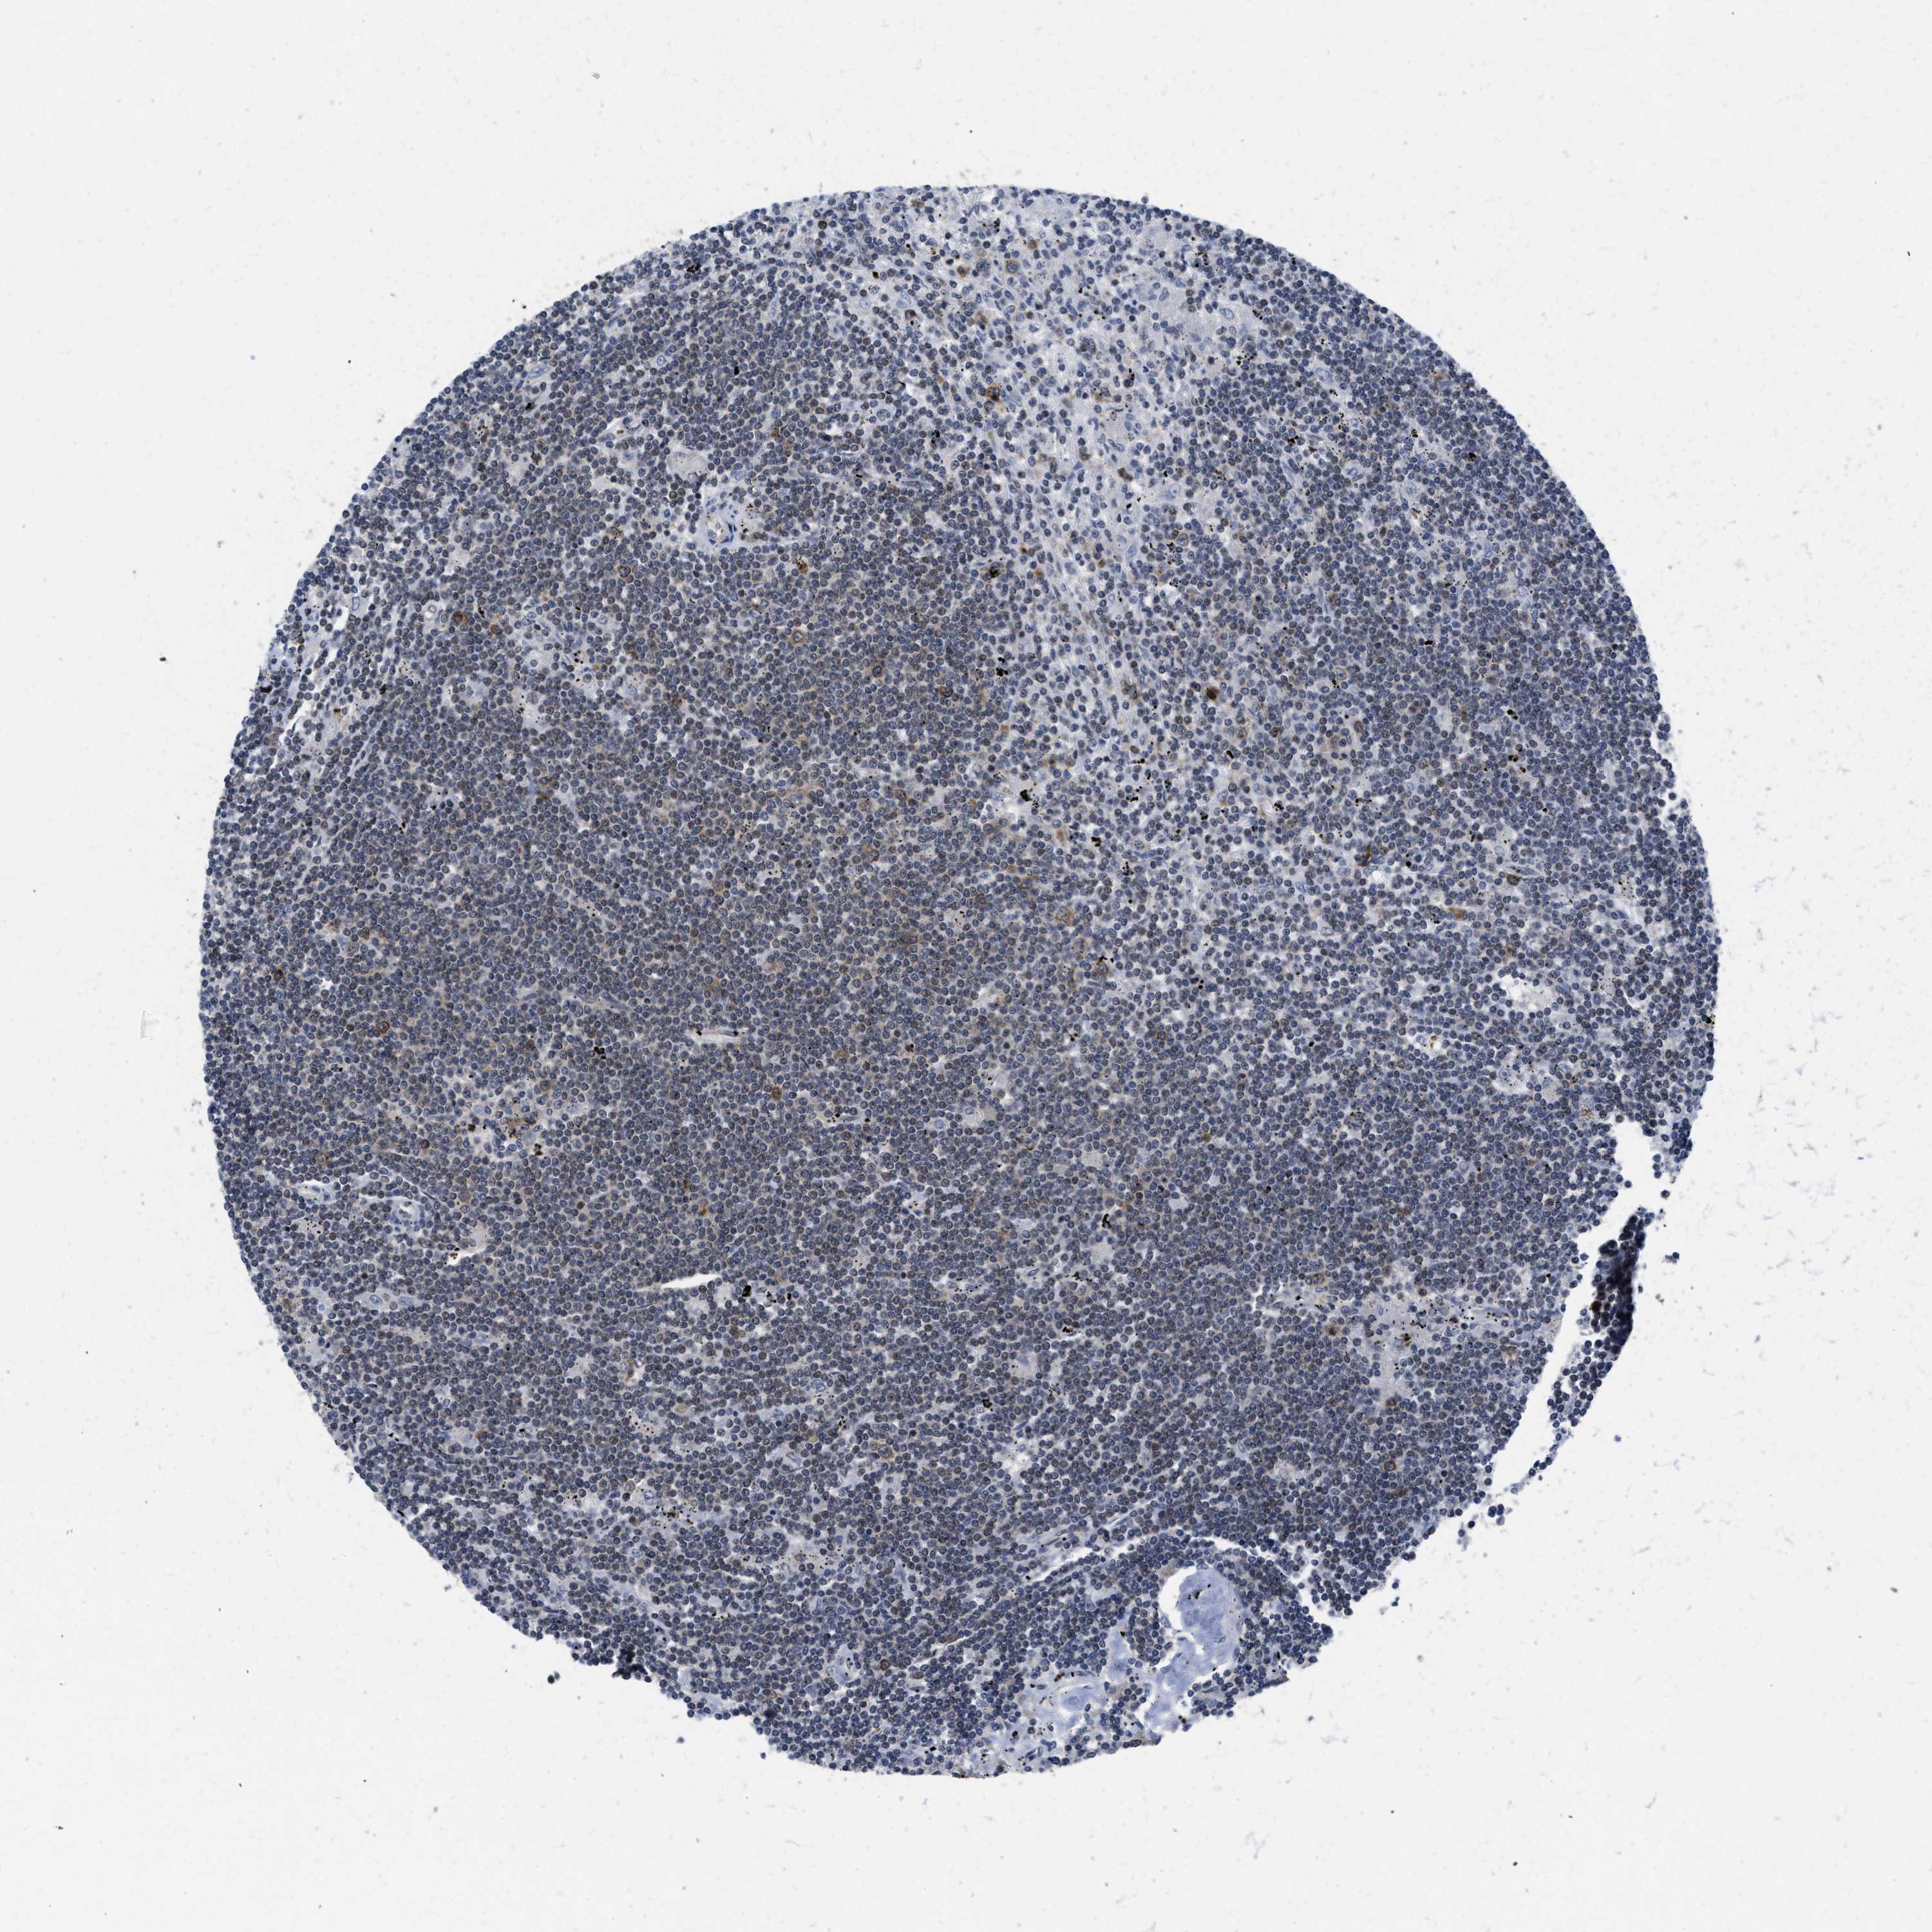

CANCER LYMPHOMA Show tissue menu

LYMPHOMA - Protein expressioni

A mouse-over function shows sample information and annotation data. Click on an image to view it in a full screen mode. Samples can be filtered based on level of antibody staining by selecting one or several of the following categories: high, medium, low and not detected. The assay and annotation is described here.

Each image is clickable and will lead to virtual microscopy that enables deeper exploration of all samples and also displays staining intensity scores, fraction scores and subcellular localization as well as patient and tissue information for each sample.

Antibody HPA001275

Antibody CAB017442

Malignant lymphoma, non-Hodgkin's type, High grade

Hodgkin's disease, NOS

Malignant lymphoma, non-Hodgkin's type, Low grade